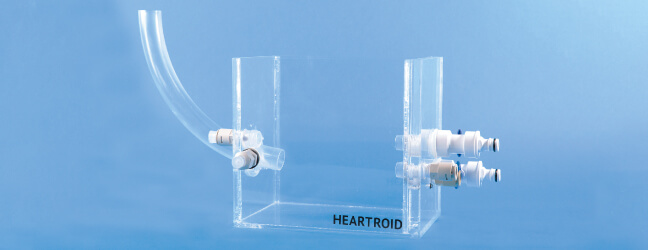

TEE対応ワイドタンク

経食道エコーに対応したタンクです。X線透視下、非透視下での視認性を考慮した透明アクリルタンクです。

TEE対応ワイドタンク

経食道エコーに対応したタンクです。X線透視下、非透視下での視認性を考慮した透明アクリルタンクです。